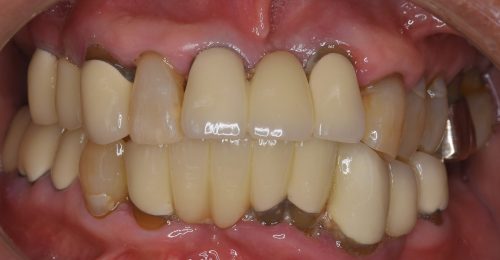

オールオン4 All-on-4

オールオン4は、4本のインプラントで上顎または下顎の人工歯列を支える方法です。従来の多数本インプラントよりも少ない本数で治療できるため、身体的負担や治療期間、費用を抑えられることが特徴です。

オールオン4では、インプラントを斜めに埋め込むことで噛む力を広く均等に分散し、最小4本のインプラントで上顎または下顎の全ての人工歯を支えることができます。日帰りで手術が可能なため、患者さまの身体的な負担も軽減され、手術当日に仮歯を装着できます。わずか1日で口元の機能と見た目が改善され、これまでの歯に関する悩みから解放されます。多くの歯を失った患者さまにとって、治療にかかる時間や費用、身体の負担を最小限に抑えながら、安定した噛み心地と自然な見た目を実現できる治療法です。